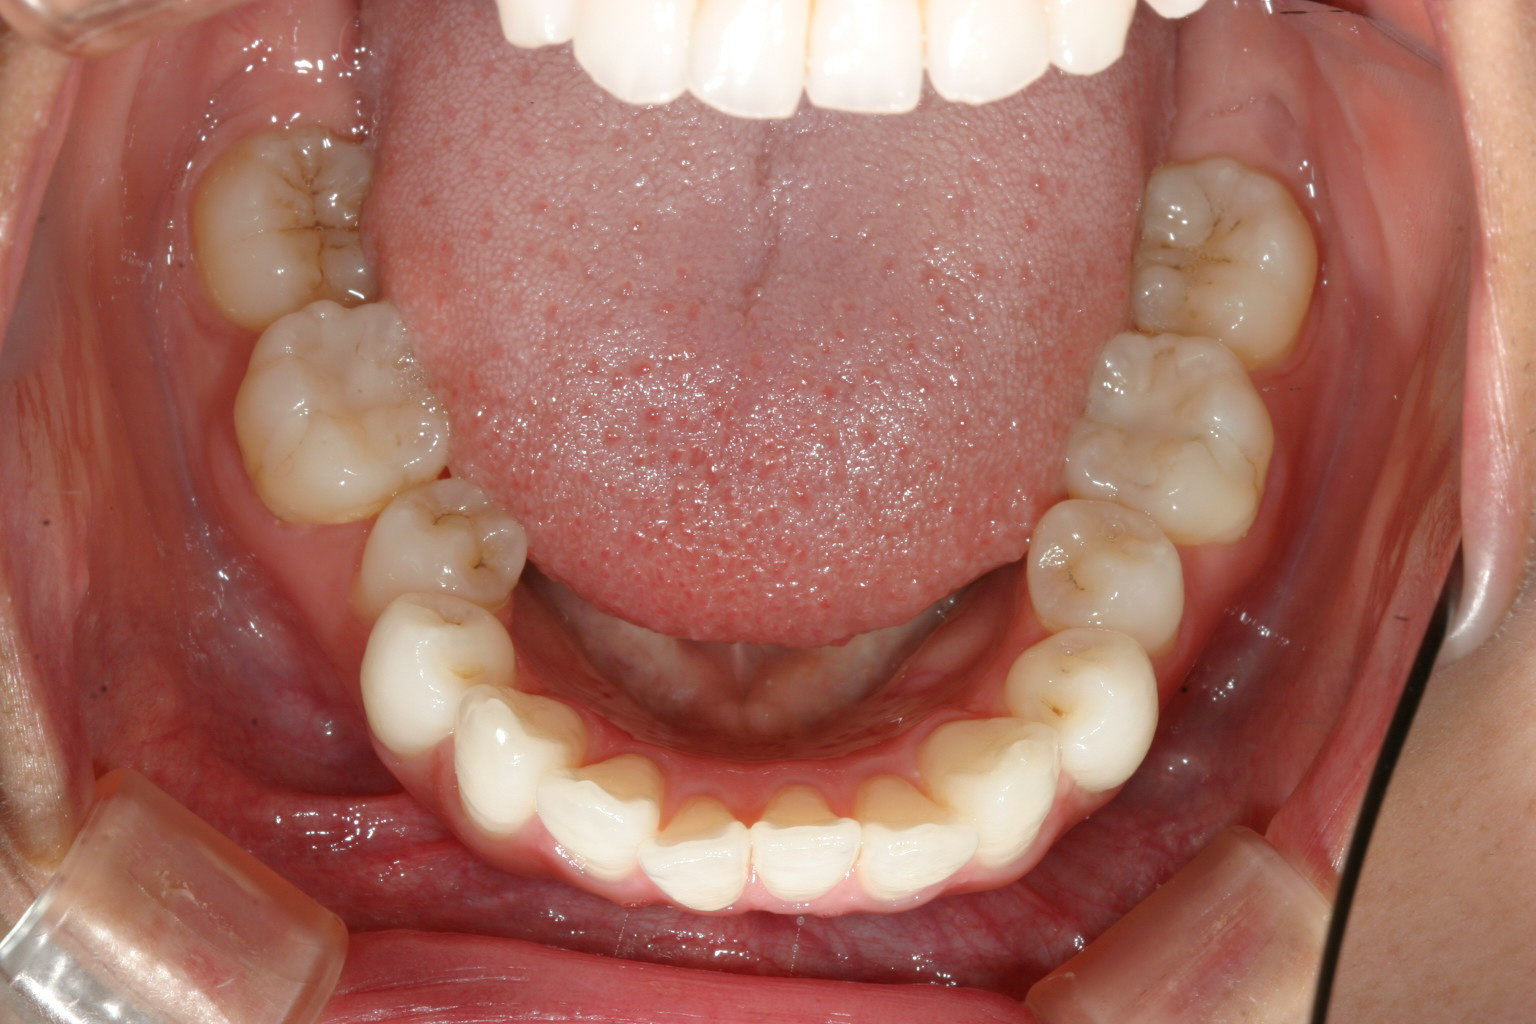

下顎小臼歯部が少しガタついてます。

横から見るとかなり前に出てるのが分かります。